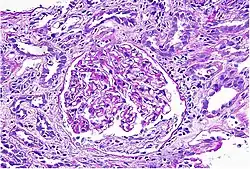

• Biopsia renal: permite el diagnóstico definitivo. Se realiza si hay dudas significativas respecto a la causa de la enfermedad renal, revela infiltración intersticial y tubular extensa con leucocitos, neutrófilos y eosinófilos.[2][4]